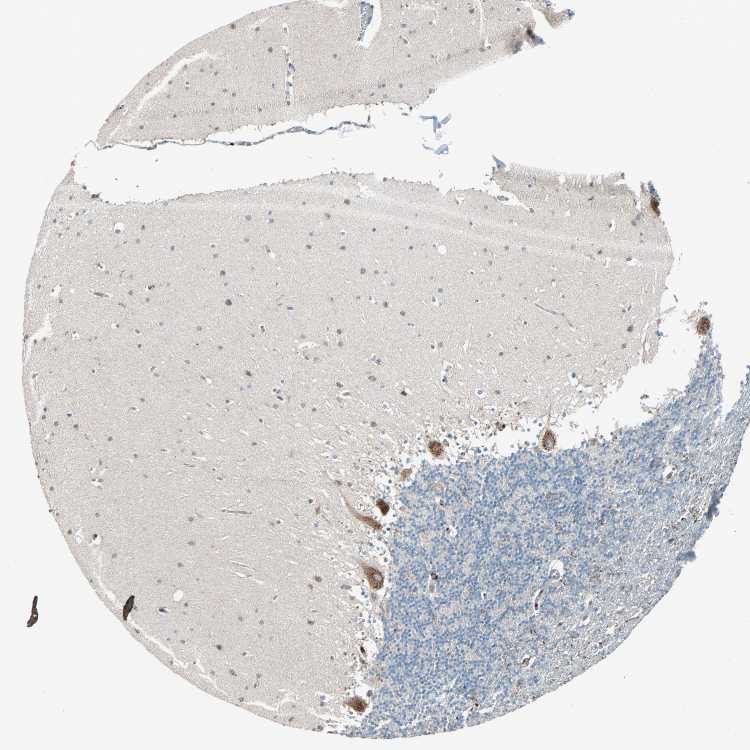

CEREBELLUM - Antibody stainingi

Antibody staining in the annotated cell types in the current human tissue is reported as not detected, low, medium, or high, based on conventional immunohistochemistry profiling in selected tissues. This score is based on the combination of the staining intensity and fraction of stained cells.

Each image is clickable and will lead to virtual microscopy that enables deeper exploration of all samples and also displays staining intensity scores, fraction scores and subcellular localization as well as patient and tissue information for each sample.

Antibody HPA007598Antibody HPA011796

Purkinje cells HighLow

Cells in granular layer Not detectedMedium

Cells in molecular layer LowNot detected